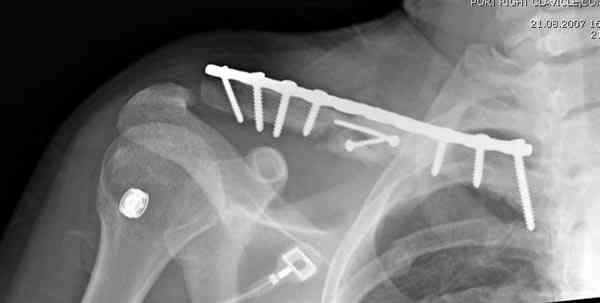

Преимуществами оперативного лечения (фиксация пластиной) является более низкий риск несращения и неправильного сращения, лучший функциональный результат к 1 году. Отрицательный момент - более

длительный период восстановления трудоспособности, необходимость в повторных операциях по удалению железа. С другой строны, большинство неправильно сросшихся переломов асимптомны, дискомфорт в области плеча, надплечья может возникать при укорочении более 1,5- 2 см, кроме того, отсроченные вмешательства при признаках несращения приводят к такому же функциональному результату, что и вмешательства в ранние сроки.

Мне представляется, что консервативное лечение предпочтительнее, за исключением случаев косметического дефекта, угрозы прободения отломком кожи, учитывая, кончено, требования пациента

При оперативном лечении ключицы необходимо применить методику Inderect Reduction Technique с обнажением кости только с той стороны, где устанавливается пластина.

При чем западные мсследования касаются большей частью сравнения остеосинтеза пластиной с консервативным лечением. У нас же в стране каждый оперирует по собственному разумению : пластинами, различными стержнями, спицами (что кстати и случилось у этого пациента)и т.д. с совершенно непрогонозируемым результатом